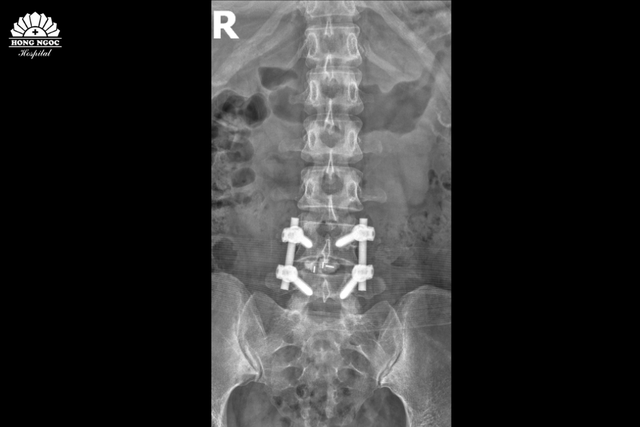

Sau gần 2 giờ, ca phẫu thuật đã thành công nhờ sự phối hợp nhịp nhàng giữa PGS.TS.BS Hà Kim Trung và Ths.Bs Lê Ngọc Anh cùng toàn bộ ê - kíp. Giúp loại bỏ toàn bộ khối thoát vị, không gây ảnh hưởng đến cấu trúc cột sống và dây thần kinh xung quanh.

Phim chụp sau phẫu thuật thoát vị đĩa đệm, hàn xương và nẹp vít đốt sống L4/L5

Sau phẫu thuật, bệnh nhân đã có thể cử động tay chân bình thường, không còn cảm giác đau hay tê buốt. Đi lại nhẹ nhàng sau 2 ngày, tự chủ trong sinh hoạt và xuất viện sau 7 ngày điều trị. Hai tuần sau, bệnh nhân đã quay trở lại công việc văn phòng với tình trạng sức khỏe ổn định và tinh thần thoải mái.